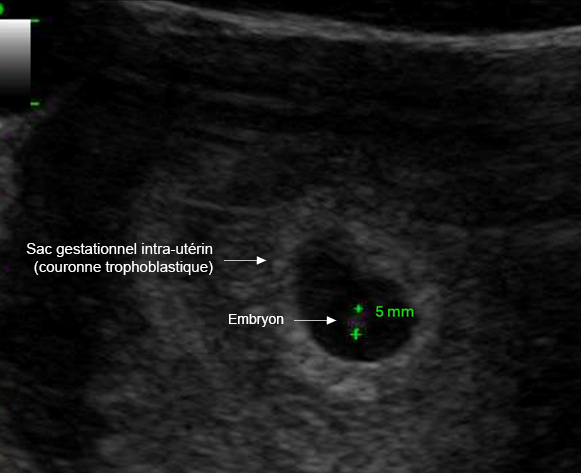

– testostérone : recherche d’une tumeur surrénale ou d’un syndrome des ovaires polykystiques (SOPK).